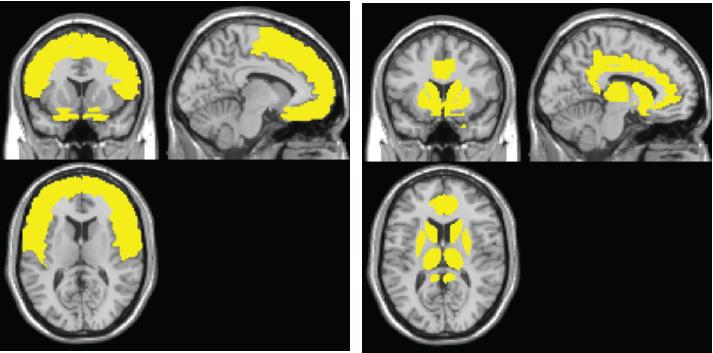

The model shows the sweep of atrophy that occurs as time passes from initial viral infection. It suggests that early on in HIV+ disease, the virus affects the frontal lobe, considered to be the essential hub of brain networks, responsible for such high-level tasks as attention and executive and cognitive functioning. By contrast, the injury to the caudate/striatum area, a subcortical region and part of the motor and reward system, becomes more prominent when individuals develop clinical HAND symptoms.

The researchers found that the frontal region (including anterior cingulate cortex, or ACC) is the most frequently affected brain region in HIV+ adults, whereas the neural injury to the caudate/striatum was consistently linked to neurocognitive impairment.

These results suggest a two-stage model of HAND in the context of brain atrophy, with a frontal/ACC stage that links to HIV disease and likely other comorbidities, such as substance abuse, and a caudate/striatum stage that links to neurocognitive impairment. "These two areas likely play different roles in HAND," Jiang says.